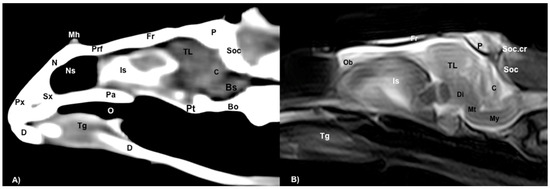

3.1. Anatomical Sections

3.2. Computed Tomography (CT)

3.3. Magnetic Resonance Imaging (MRI)